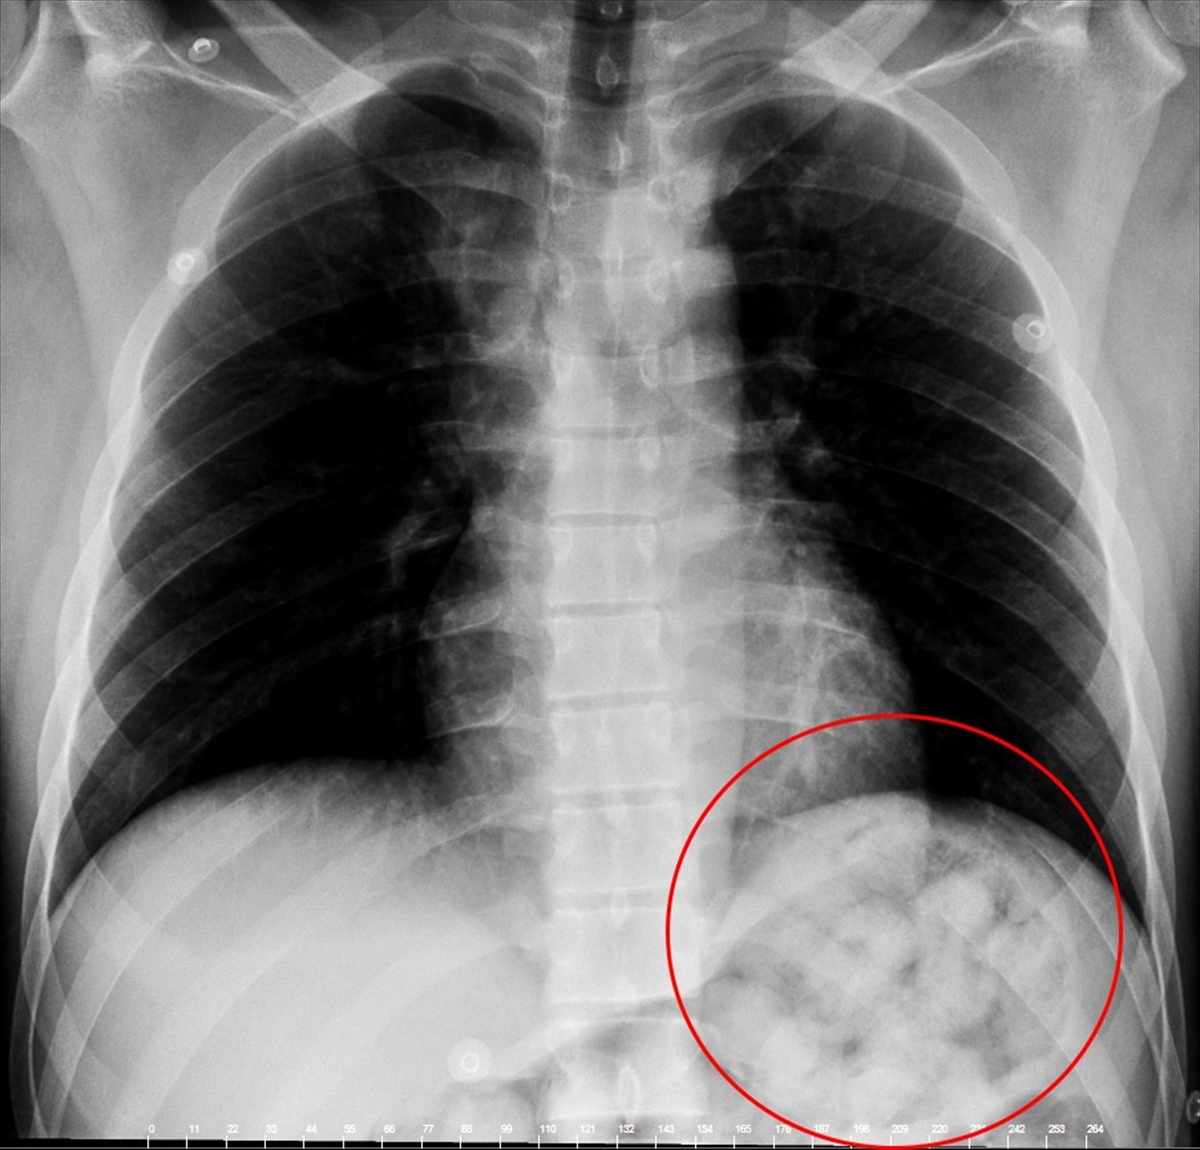

Narziveh'in röntgen filmlerinde midesinde uyuşturucu madde kapsülleri görüldü. Bunun üzerine Narziveh mahkeme kararıyla ameliyata alındı.

Ameliyatın ardından şüphelinin midesinden ikisi patlamış halde 72 kapsül içerisinde yaklaşık 900 gram metamfetamin çıkarıldı.